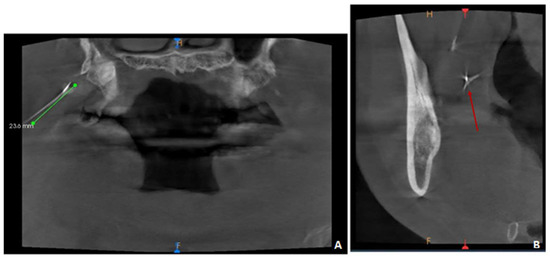

5. Case Report